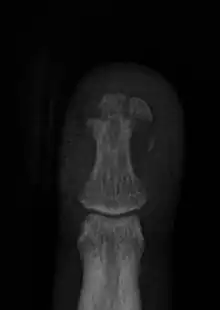

Fracture of the tuft of the finger

Finger injuries are usually diagnosed with x-ray and can get to be considerably painful. The majority of finger injuries can be dealt with conservative care and splints. However, if the bone presents an abnormal angularity or if it is displaced, one may need surgery and pins to hold the bones in place.